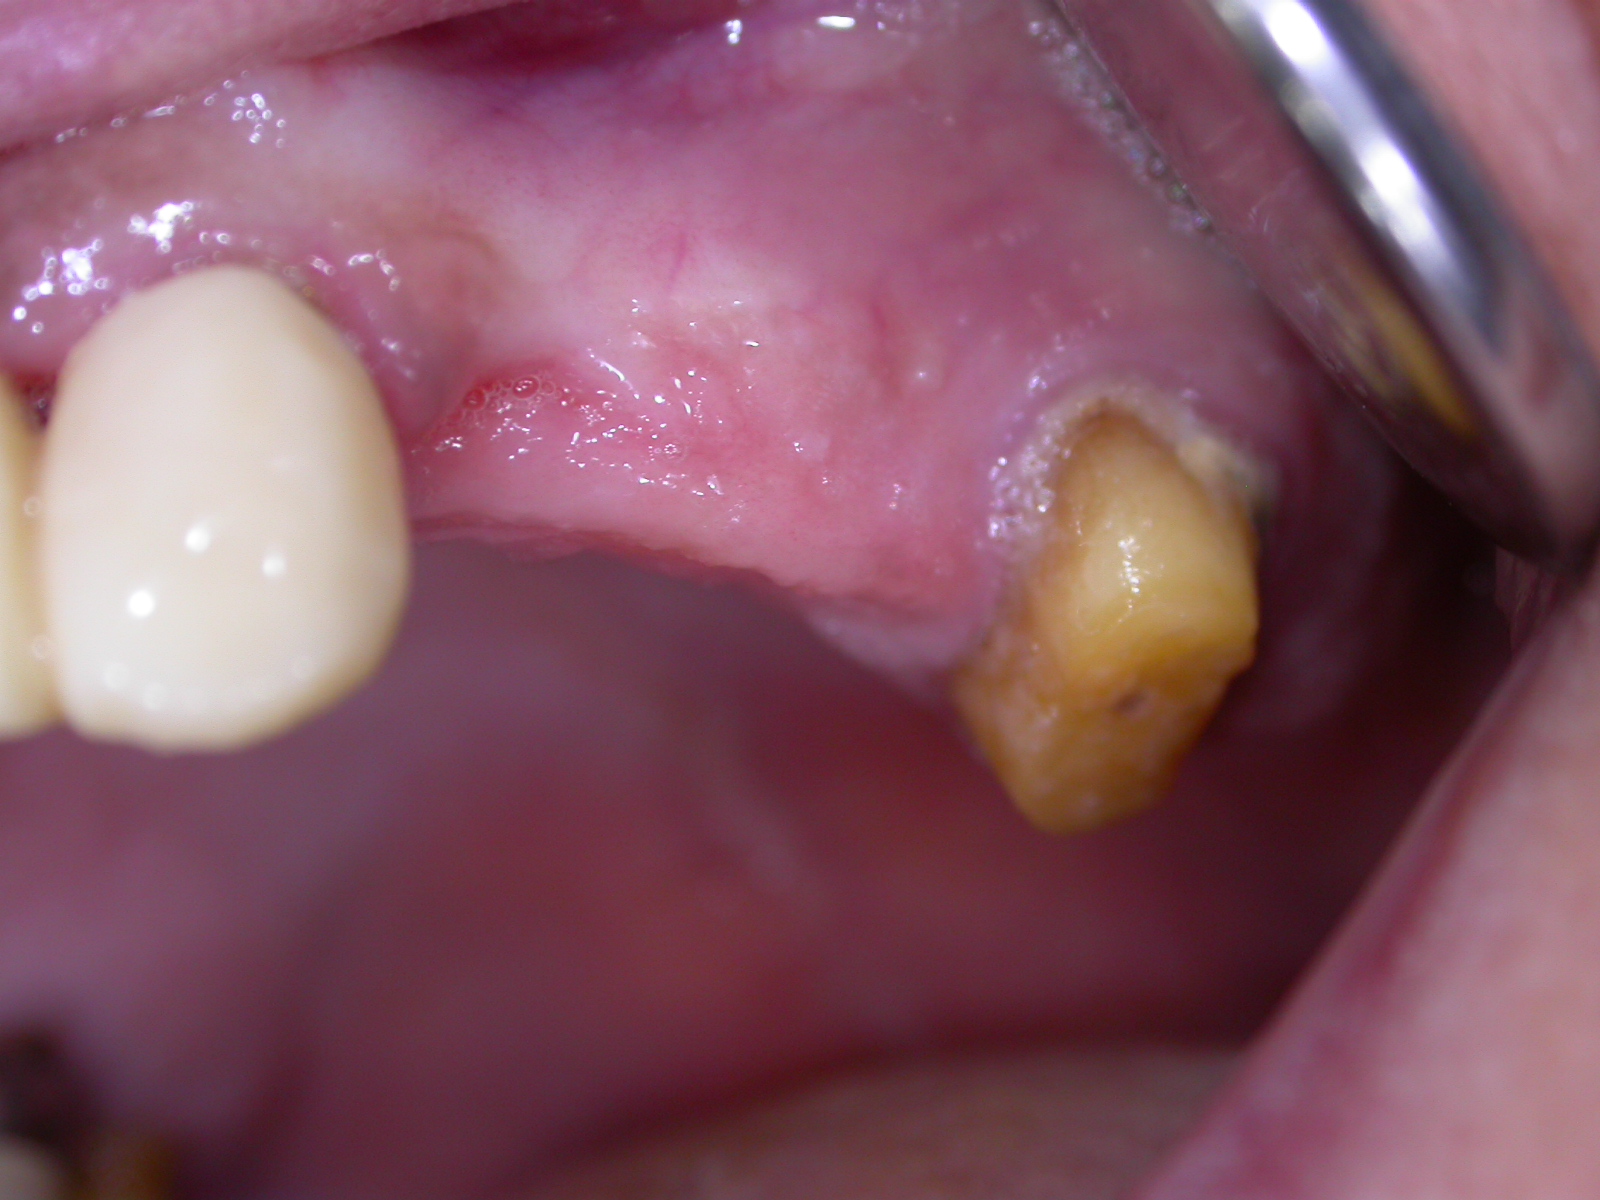

La paziente di anni 55, da me sottoposta a visita, lamentava un forte disagio estetico e funzionale in arcata superiore. Ho proposto così una riabilitazione protesica mista su denti naturali e su impianti nella zona edentula superiore sinistra.

Riabilitazione protesica mista su denti naturali e su impianti nella zona edentula superiore sinistra